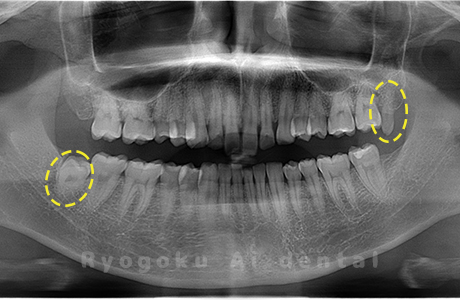

Case03

- 上顎、下顎の親知らず

- 上下4本の親知らずを抜歯したケースです。

<リスク・副作用>

手術後は痛み、腫れ、痺れなどの副作用が生じる場合があります。